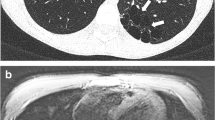

Cystic fibrosis and allergic bronchopulmonary aspergillosis in a 16-year-old girl. (a) Axial nonenhanced lung window setting CT image obtained at end-expiration shows impacted mucus and bronchiectasis (white arrowhead) in the right middle lobe. (b) Axial nonenhanced isotropic three-dimensional (3D) CUBE (GE) T2-weighted MR image obtained at end-expiration shows impacted mucus and bronchiectasis (black arrowhead) in the right middle lobe

Comparison of ultra-short echo time (UTE), zero echo time (ZTE), and CT for large airway MR imaging. (a) Axial nonenhanced lung window setting CT image obtained at end-expiration shows right upper lobe bronchiectasis and bronchial wall thickening (black arrow). (b) Axial nonenhanced free-breathing navigator-triggered zero echo time (ZTE) MR image obtained at end-expiration shows right upper lobe bronchiectasis and bronchial wall thickening (black arrow) with resolution approaching that of CT. (c) Axial nonenhanced pneumobelt-triggered ultra-short TE (UTE) MR image obtained at end-expiration shows right upper lobe bronchiectasis and bronchial wall thickening (black arrow) with resolution approaching that of CT

Comparison of 3D T2-weighted MR imaging of the airway to CT in a pediatric patient with cystic fibrosis. (a) Coronal nonenhanced lung window setting CT image shows bronchiectasis and bronchial wall thickening (arrow) in left lower lobe. (b) Coronal nonenhanced isotropic three-dimensional (3D) CUBE (GE) T2-weighted MR image shows the bronchiectasis and bronchial wall thickening (arrow) resolution approaching that of CT